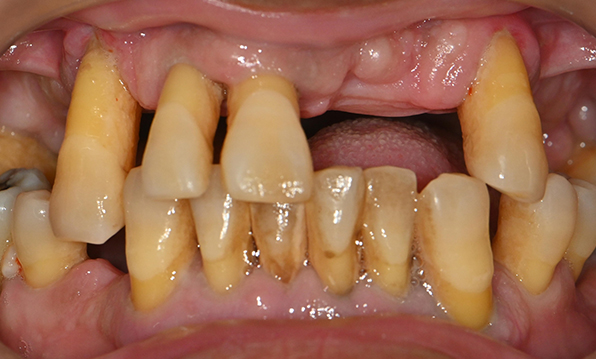

전체 임플란트가 필요한 경우

치아가 얼마 남아있지 않은 경우

치주질환이 심해, 치아가 있더라도 제 기능을 하지 못하는 경우

틀니 사용이 불편한 경우

전체 임플란트를 해야하는 환자들은

대부분 고령의 환자들로 오랜 틀니 사용

또는 노화로 인해 치조골이

거의 남아있지 않는 경우가 많습니다.

이 때, 치조골 이식을 병행하여 잇몸뼈 재건 후 안정적인 임플란트 식립을 하고 있습니다.

치료기간 : 2021.04.12~2021.09.15